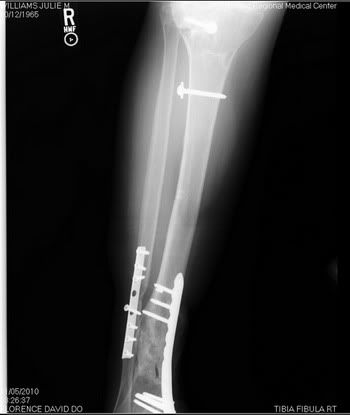

Most people don't understand why I am the way I am. I hope these x-rays give them a better idea of what I have to deal with every single day.

My right tibia (shin)